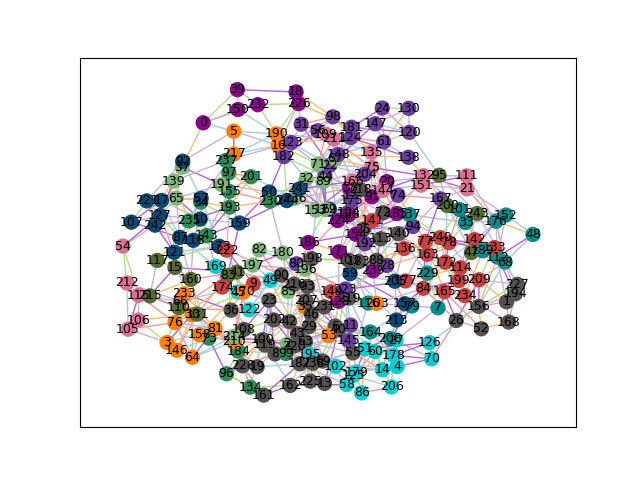

(b) Graph example

Figure 2: (a) Estimation of the next ES frame index using the ground truth ES and ED frames. (b)Example graph for the Hyperdynamic class generated by InfoMotion.

Graph construction: To identify representative videos that capture both essential information and the diversity of the dataset, we construct a weighted graph Gc=(Mc,E,w)G_{c}=(M_{c},E,w) for each class cc, where Mc={Mci}i=1NcM_{c}=\{M_{c}^{i}\}_{i=1}^{N_{c}} is the set of nodes. Each node MciM_{c}^{i} corresponds to the motion feature vector of a video and NcN_{c} denotes the total number of videos in class cc. The edges EE connect pairs of nodes, and the edge weights ww are given by the Euclidean distance between their motion feature vectors. We construct CC separate graphs, one for each class, ensuring class-specific representation in the selection process.

Infomap search: Once the class-specific graphs are constructed, our objective is to identify representative nodes that capture the diversity and structure of each class. For this, we use the Infomap algorithm [blocker2023map], which is well-suited for analyzing weighted graphs and uncovering meaningful community structures. Infomap applies the minimum description length (MDL) principle to model the movement of a random walker on the graph, partitioning it into communities that minimize the information required to describe this movement. This ability to detect informative, non-trivial community structures makes Infomap particularly effective for our motion-feature graphs. After detecting communities, we uniformly select nodes with high modular centrality from each community. Modular centrality is a scalar metric that combines intra-community and inter-community influence scores [ghalmane2019centrality], ensuring that selected nodes are both locally representative and globally influential. The resulting set of videos forms the distilled synthetic dataset used for downstream training. Fig. 2(b) shows an example output of the Infomap search, where nodes of the same color belong to the same community.